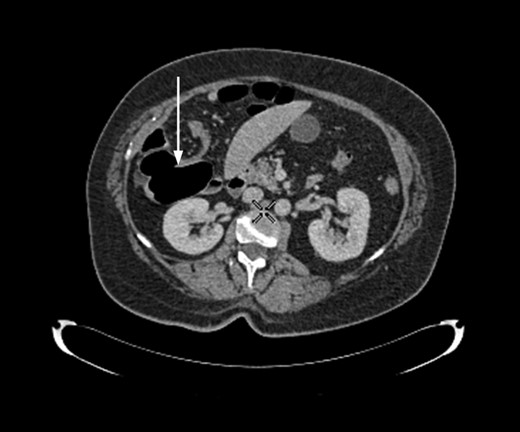

Axial section of contrast-enhanced CT demonstrating ‘whirl sign’ at the point of volvulus.

Radiological imaging is useful in diagnosing caecal volvulus. Rosenblat et al. [8] found that CT findings of whirl, ileocaecal twist, transition points, X marks the spot and split wall have high specificity for caecal volvulus. Additionally, they found that the absence of distal colonic decompression made the diagnosis of caecal volvulus unlikely. Diagnostic confusion may exist between sigmoid and caecal volvulus; however, the location of the mesenteric twist (CT whirl sign) is highly accurate in distinguishing the two [9]. This whirl sign, as first published by Fisher [10], describes ‘swirling strands of soft tissue attenuation within a background of fat attenuation and gives the appearance of a hurricane on a map’. Barium enema has been historically used to confirm the presence of a volvulus, assess the distal colon and may also have a therapeutic effect [3].